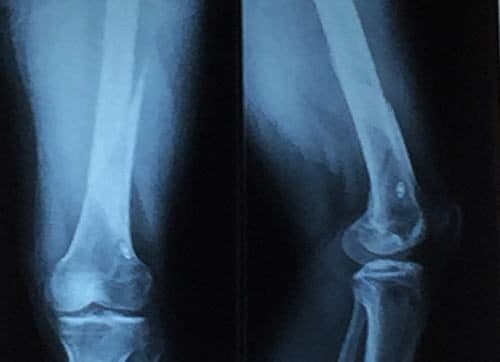

Chụp X quang khớp gối

Chụp X quang khớp gối giúp phát hiện các bất thường ở đầu gối và hỗ trợ điều trị bệnh hiệu quả. Do lo ngại tác hại của chụp X quang nên nhiều người muốn tìm một địa chỉ thăm khám uy tín và hiệu quả. Để có cho mình địa chỉ thăm khám khớp gối […]